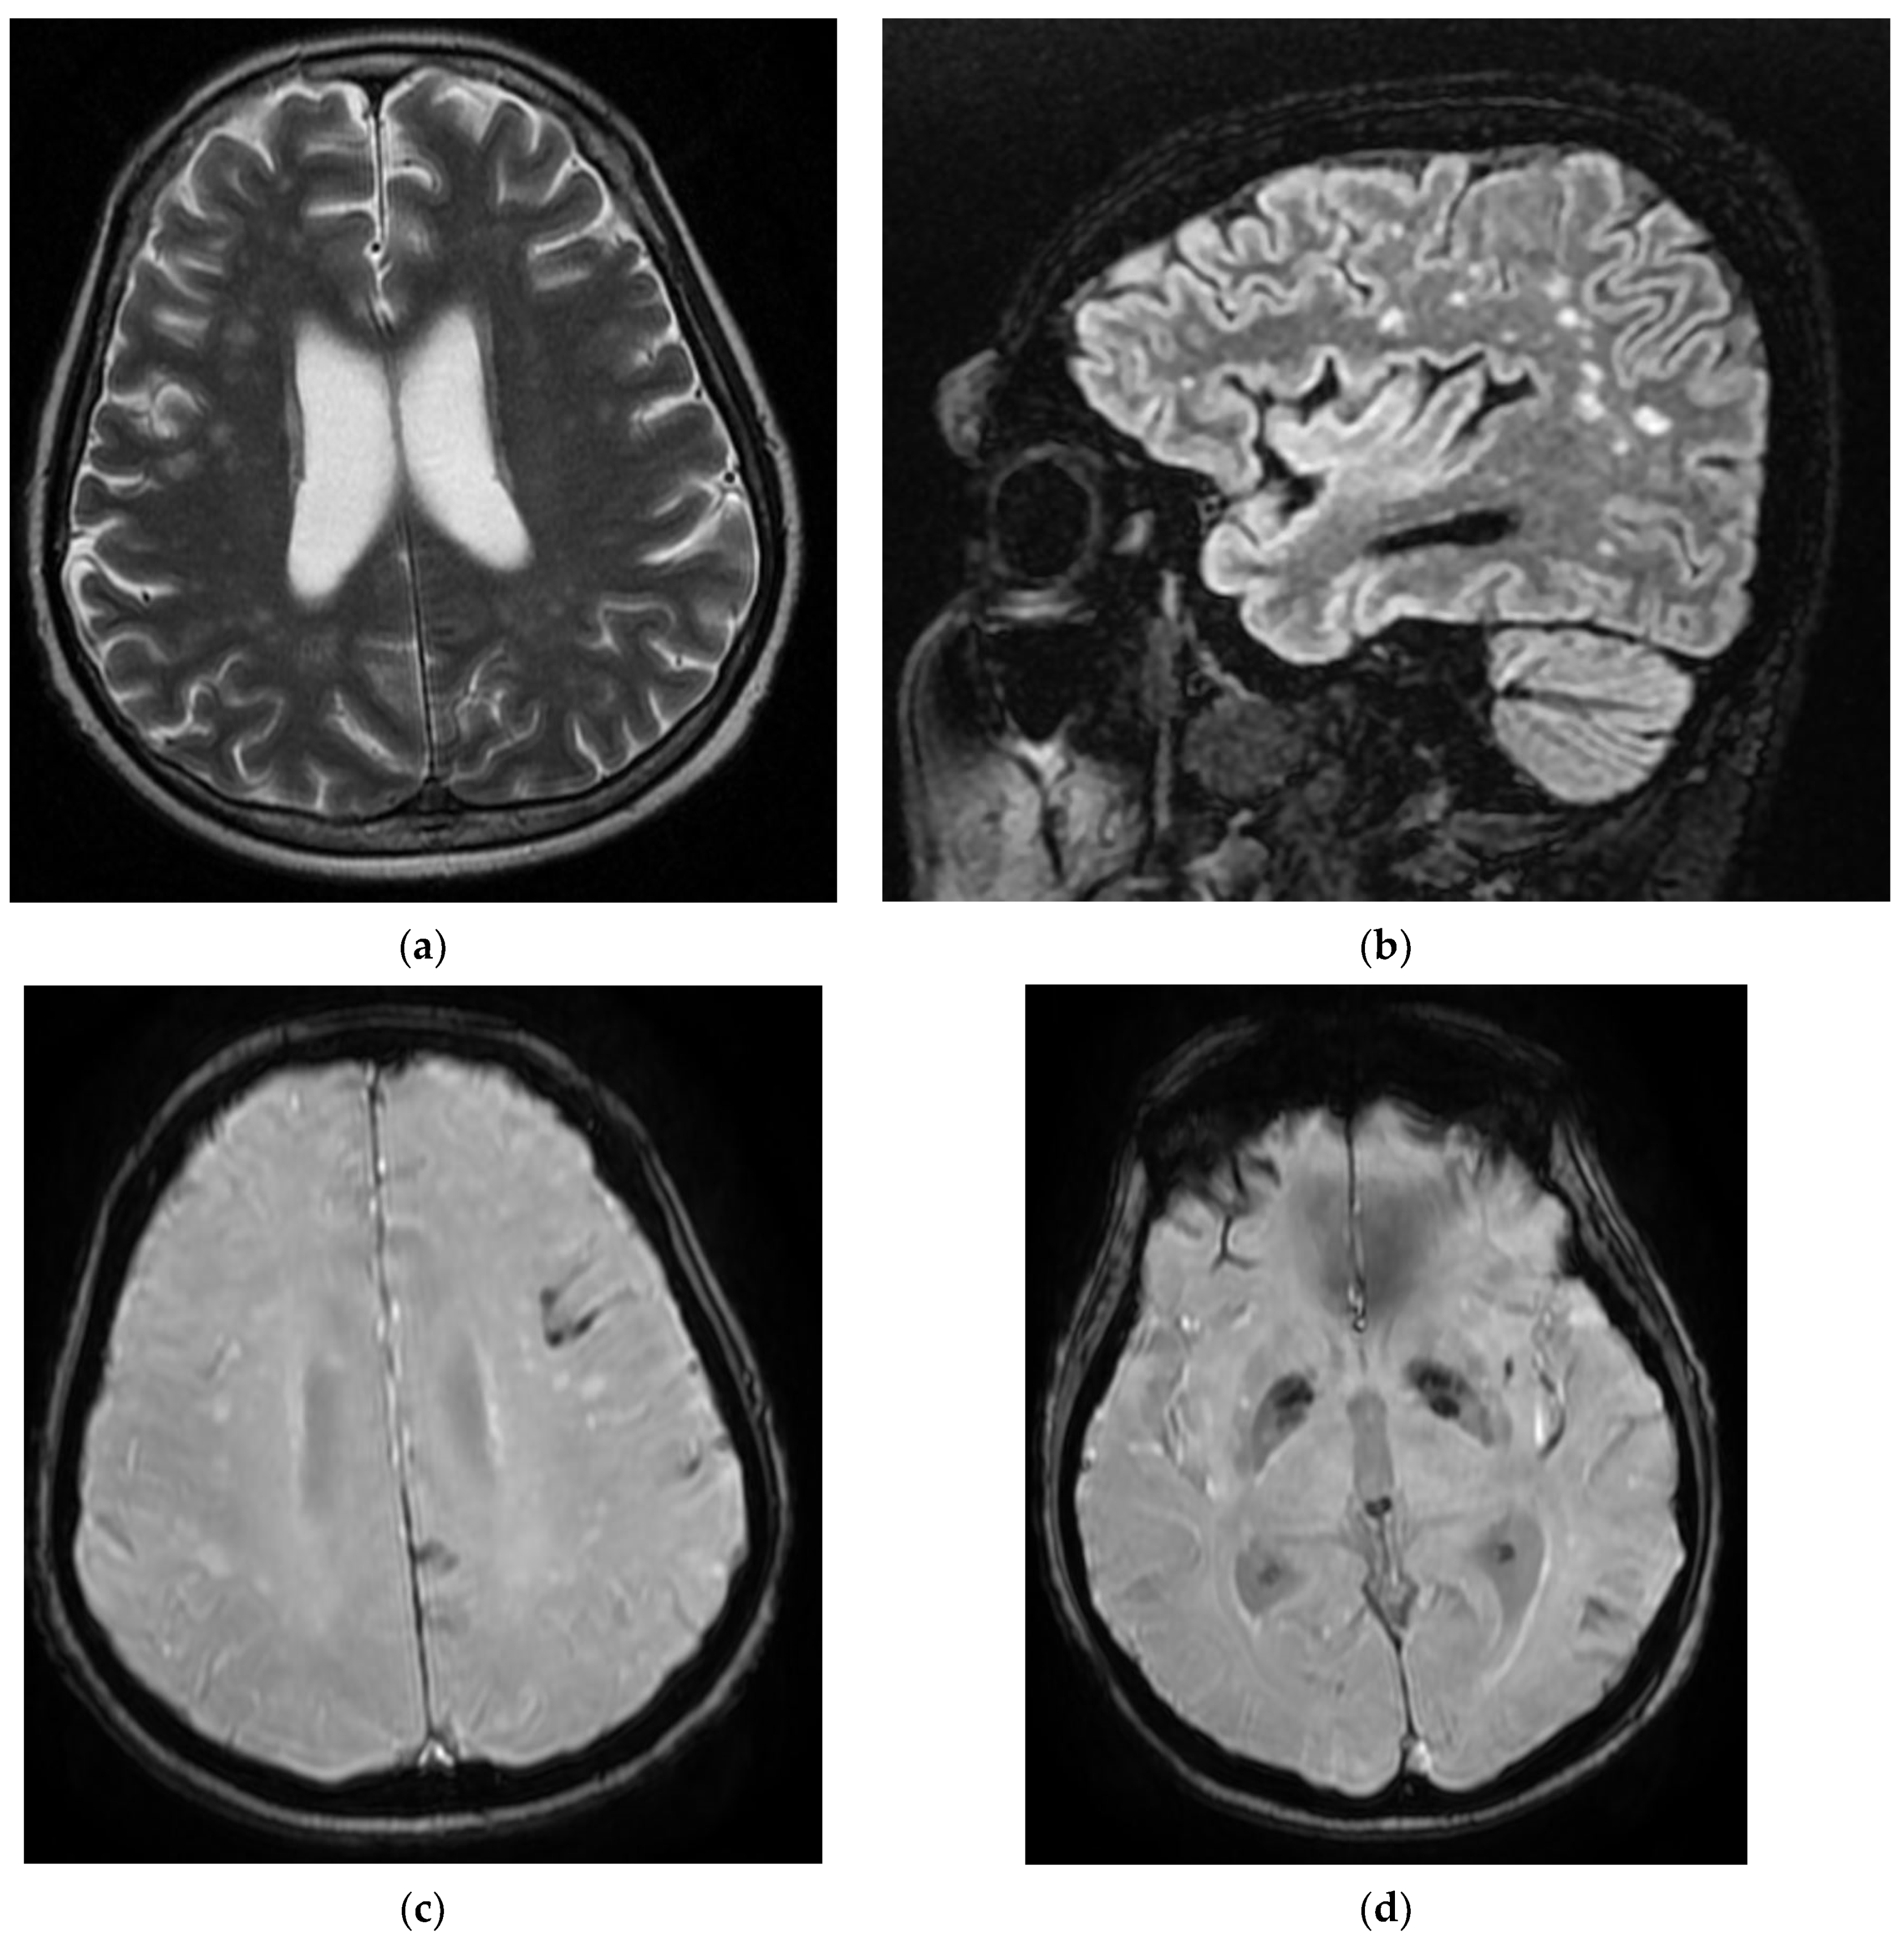

Figure 3. MRI images of the Case 3 patient reveal multiple centimetric lesions in T2/FLAIR hypersignal (a,b), with no diffusion restriction, disposed in a white hemispheric substance in the bilateral subcortical frontal–temporal–parietal area, as well as in the right cerebellar hemisphere, and supratentorial demyelinating lesions most probably with an ischemic vascular sublayer. Additionally, linear and curvilinear traces in SWAN signal (c,d), disposed in the left cortical parietal, frontal area–frontal cortical and left parietal hemosiderosis.